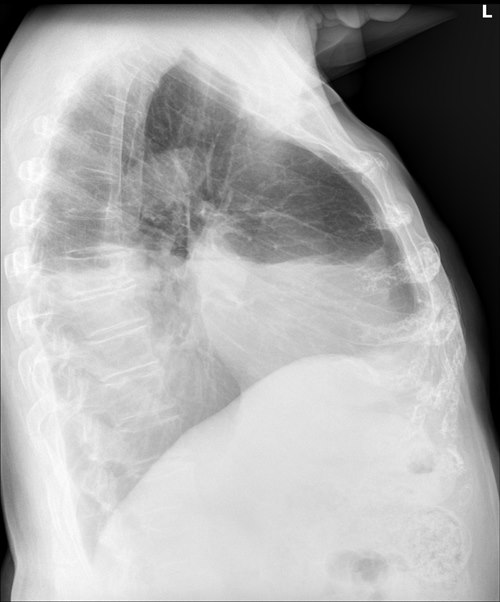

RTG klatki piersiowej

- Płyn w opłucnej można wykryć w projekcji tylno-przedniej, jeżeli obecne jest co najmniej 200 ml płynu, a na zdjęciach w projekcji bocznej już przy 50 ml płynu.2

- W przypadku nagromadzenia dużej ilości płynu może dojść do przemieszczeń w śródpiersiu.

- W ponad 80% przypadków niewydolności serca występuje obustronny przesięk opłucnowy.